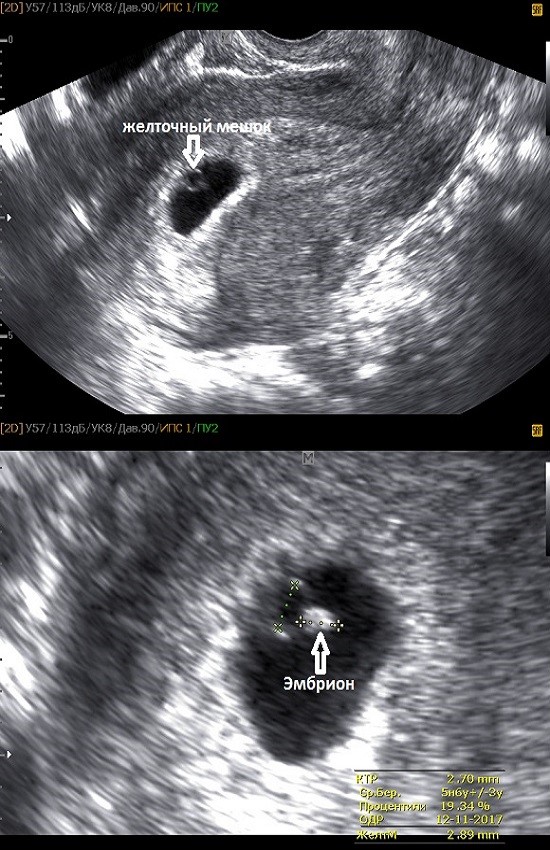

На основании приказа Минздрава России от 07.04.2016г №216н «Об утверждении формы информированного добровольного согласия на проведение искусственногопрерывания беременности по желанию женщины» проводится обязательное ультразвуковое исследование органов малого таза с демонстрацией изображения и сердцебиения эмбриона плода (при наличии сердцебиения) при сроке беременности 6недель. Отсутствие сердцебиения эмбриона плода считается признаком смерти, однако необходимо помнить, что у очень малого по размерам эмбриона (˂ 4мм) сокращения сердца могут не выявляться, поэтому УЗИ необходимо будет повторно провести спустя несколько (2-3) дней, чтобы подтвердить первое впечатление.

Значение длины эмбриона 5мм является пороговой величиной, выявленной при УЗИ, при которой сердечная активность должна визуализироваться во всех случаях

Первое УЗИ проводится на сроке от 3 недель и представляет собой знакомое всем женщинам трансвагинальное исследование (с использованием влагалищного датчика). Это обследование позволяет подтвердить беременность, установить количество плодов и проследить за сердцебиением эмбриона.